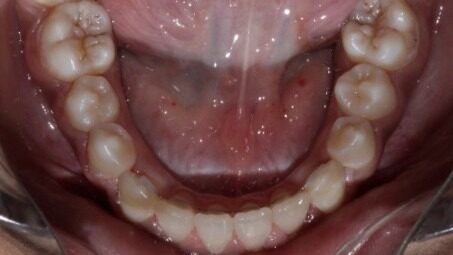

During The Treatment

After: Lower